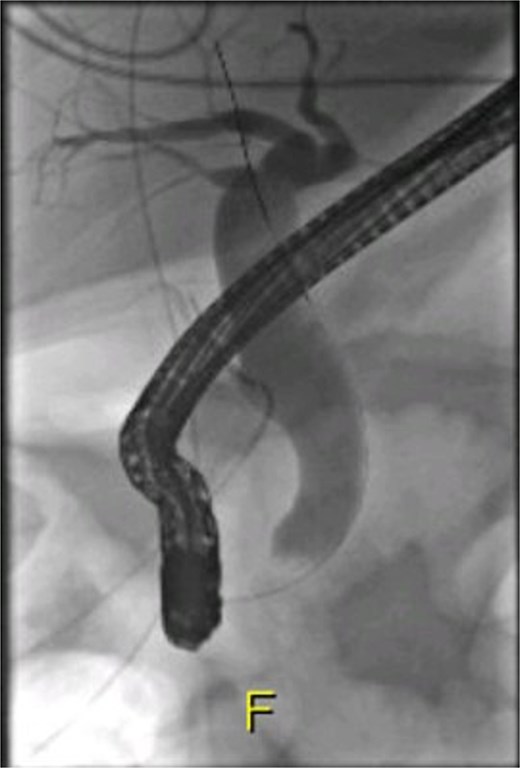

Following surgical intervention, the patient was admitted to the intensive care unit (ICU), where she was closely monitored for three days before being stepped down to the ward. During this time, her labs normalized, and drain output decreased steadily. The drain was removed on post-operative day (POD) 11, and she was subsequently discharged. Notably, the cytology of CBD brushings did not reveal any malignant cells. A repeat ERCP was performed after 8 weeks, which revealed no contrast leak, indicating spontaneous healing (Fig. 5), and the biliary stent was removed. Successive clinic follow-up at 6 months post-treatment indicated that the patient remained completely asymptomatic and exhibited excellent clinical recovery.